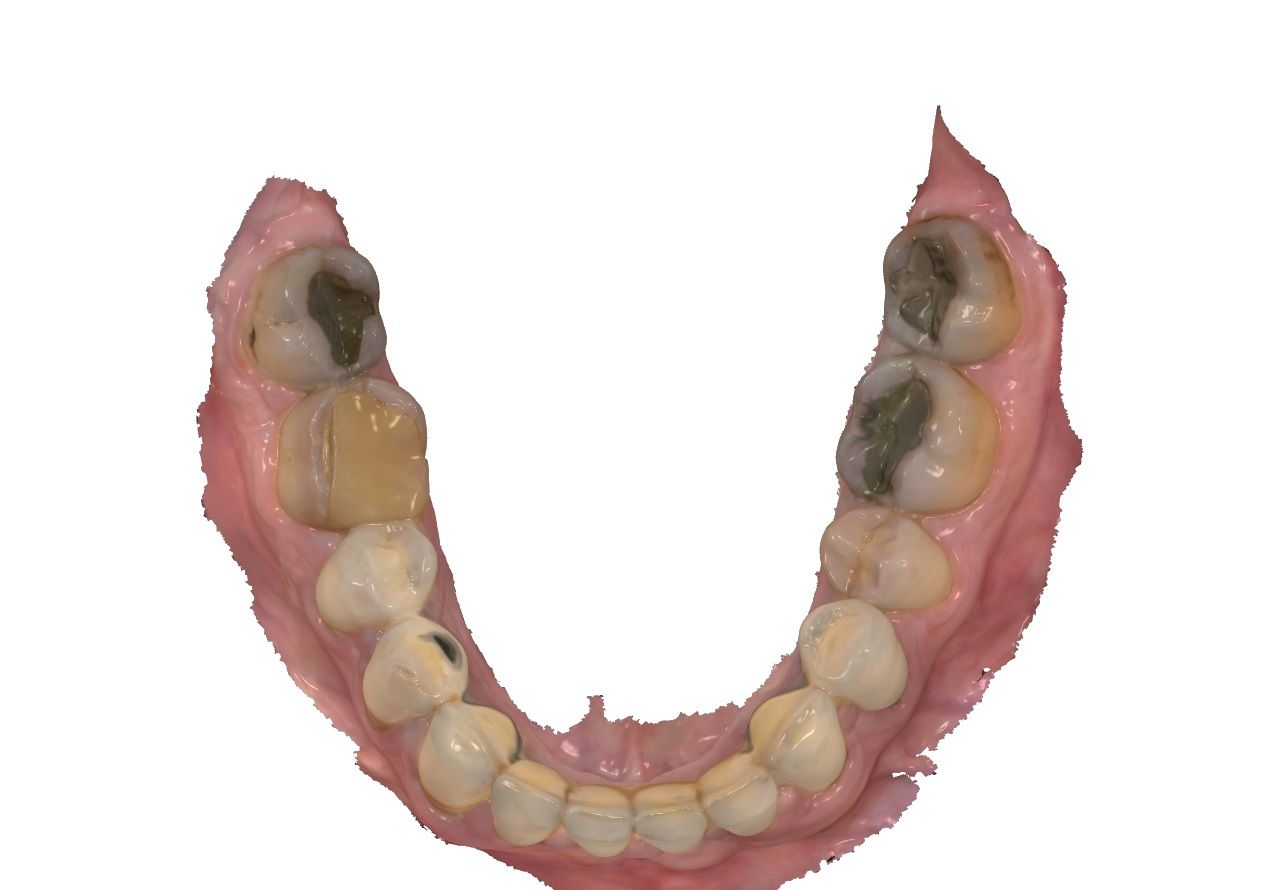

Unterkiefer

48 f f 38

47 F2 c c F2 37

46 KM ww c F2 36

45 KM kw 35

44 KM kw kw KM 34

43 KM kw kw KM 33

42 SKM b b SKM 32

41 BM b b BM 31

f c ww kw kw kw b b

b b kw kw c c f

F2 KM KM KM KM SKM BM

BM SKM KM KM F2 F2